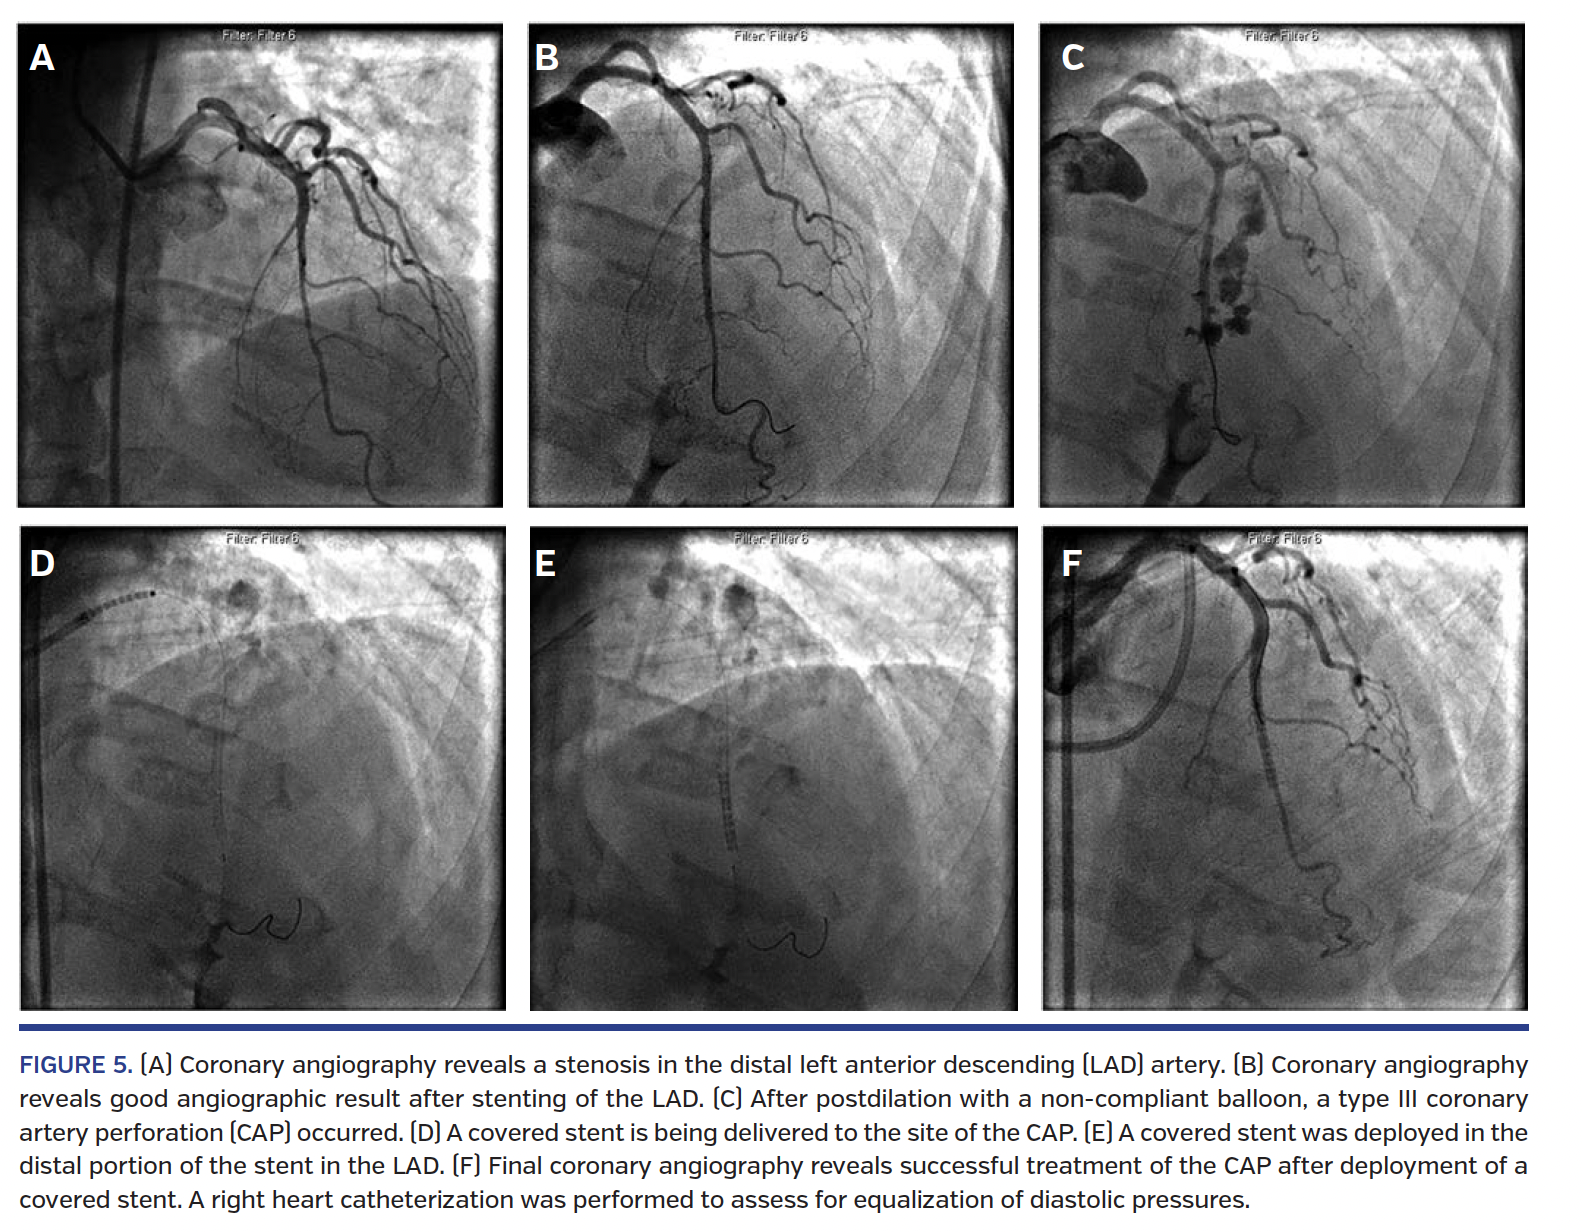

Early recognition and treatment are crucial for survival after CAP. The goal of CAP management is to seal the site of extravasation and to treat hemodynamic instability from pericardial effusion or tamponade. Although there have been proposed algorithms for CAP management,3,7,14,32,33 there is no consensus on optimal treatment of CAP and protocols may vary by institution (Figures 4 and 5). Several factors impact the management of CAP, including CAP grade, presence/duration of pericardial effusion or tamponade, and hemodynamic status.

Covered stents. Polytetrafluoroethylene (PTFE)-covered stents consist of a balloon-expandable layer of PTFE between two stainless-steel stents that prevent blood leakage between stent struts.3 PTFE-covered stents decrease the incidence of in-hospital major adverse cardiac events in type III CAP.10 In a multicenter study of patients in whom reversal of anticoagulation and prolonged balloon inflation were unsuccessful, use of PTFE-covered stents vs non-covered stents led to less need for CABG (18% vs 88%, respectively; P<.001), tamponade (8% vs 82%, respectively; P<.001), and major adverse cardiac events (18% vs 88%, respectively; P<.001).46 An international retrospective registry of CAP treated with PTFE-covered stents reported a success rate of 92.9% for completely sealing CAP.47 No in-hospital Q-wave myocardial infarction, emergent CABG, or deaths were reported. The disadvantage of covered stents is that they are bulky and rigid, making them difficult to deliver in calcified and tortuous vessels, particularly in emergency situations and in arteries <2.75 mm in diameter.32 However, one study has shown no difference in rates of tamponade, emergency CABG, and in-hospital death with the use of PTFE-covered stents compared with perfusion balloons and non-covered stents.16 Dual-antiplatelet therapy with aspirin and clopidogrel should be continued for at least 6 months to minimize the risk of stent thrombosis.32

As little as 100 mL of fluid accumulation in the pericardial space, in an acute setting, can cause hemodynamic instability.39 Tamponade should be suspected when patients develop hypotension, chest pain, shortness of breath, dizziness, bradycardia, or engorged neck veins. The key to diagnosis and evaluation is emergent bedside echocardiography. Right heart catheterization can facilitate the diagnosis of tamponade, looking specifically for equalization of diastolic pressures.